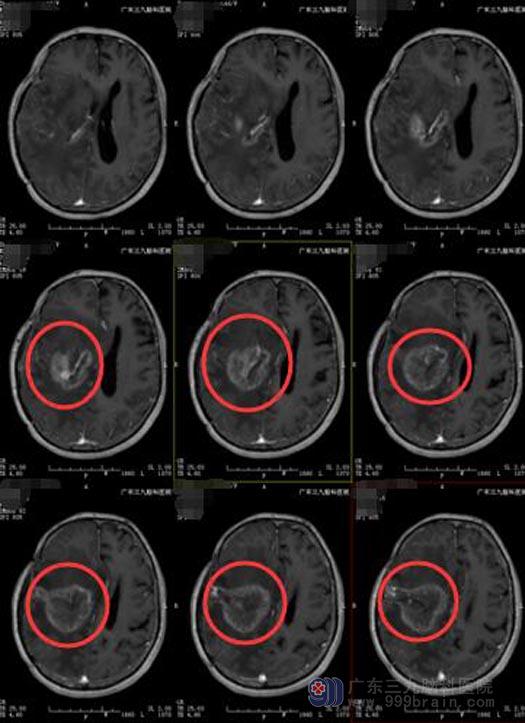

广东三九脑科医院进一步MR检查提示:右侧顶叶胶质瘤外院术后放化疗后,右侧额顶部呈术后改变,右侧额叶术区示片状长T1长T2异常信号影,FLAIR序列呈不均匀等、稍高信号,增强后呈明显花环状异常强化影,范围约为6.4cm×5.2cm×5.5cm,序列呈高信号,累计右侧丘脑及脑干偏右侧。右侧大脑镰下疝形成。

手术前